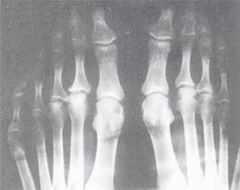

如今稍有醫學常識的人都知道,風濕性關節炎是一種自身免疫病,病人的免疫系統錯把自己的關節組織當成了敵人,並實施攻擊,結果造成了關節發炎,紅腫僵硬,嚴重的病人根本無法行走,失去活動能力,非常痛苦。可在上世紀初的時候,風濕性關節炎還被看做是某種細菌感染造成的。幸虧當時抗生素還沒有被發現,否則醫生們肯定會給每個關節炎病人打一針青黴素。

關節炎1928年,美國明尼蘇達大學馬約醫學院的藥劑系系主任菲利浦.亨奇(PhilipHench)接待了一位奇怪的病人,這位65歲的病人其實是該醫院的醫生,他告訴亨奇一件奇怪的事情:自從他得了黃疸病,他的風濕性關節炎症狀就消失了。4個星期之後,他的黃疸病治好了,但是他的關節炎直到7個月後才再次復發。

1948年7月26日,亨奇把100毫克化合物E注射進一位患了嚴重的風濕性關節炎的女病人體內,2天之後病人的症狀有了明顯的好轉,她居然能夠自己行走了,而以前她只能坐輪椅。後來有人指出,亨奇違反常規,用了超大劑量的化合物E,否則的話療效不可能如此顯著。